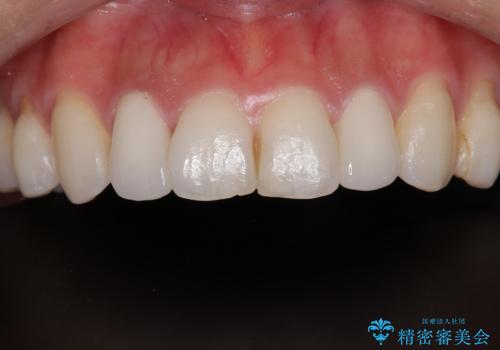

- 前歯の変色が気になるので、きれいにしたいことを主訴として来院された患者様です。

もともと矮小歯で歯の大きさが小さいことが気になっていましたが、改善されて満足されました。